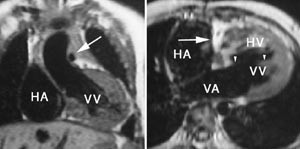

MR har potensial til å spille en viktig rolle i utredningen av de fleste medfødte hjertesykdommer (3, 8), men undersøkelsens betydning er langt på vei bestemt av i hvilken grad man lykkes med ekkokardiografi, som alltid vil være førstevalg blant de bildediagnostiske metodene. En generell ulempe ved MR-undersøkelse av små barn (som ikke kan ligge stille) er behovet for sedering eller anestesi. MR har sin styrke først og fremst i oversiktlig fremstilling av komplisert anatomi, ikke minst relasjonen mellom de store kar og hjertets ulike avsnitt. Metoden er derfor særlig til nytte ved de mer komplekse medfødte feil (fig 5). MR kan også gi verdifull funksjonell informasjon så som ventrikkelvolum og myokardmasse, ejeksjonsfraksjon, klaffefunksjon, minuttvolum, evaluering av shunting og beregning av gradienter. Vurdering av høyre ventrikkels funksjon er ofte et problem ved medfødte hjertefeil, og MR har her et betydelig potensial. Ved kontroll av postoperative forhold, spesielt hos ungdom og voksne, vil MR ofte være den foretrukne metode (3, 8). Ved mer enkle feil som coarctatio aortae bør MR helt kunne erstatte invasiv angiografi med trykkmåling. I tillegg til en nøyaktig fremstilling av anatomien, kan MR også benyttes til å beregne trykkgradienten i en koarktasjon og graden av shunting forbi koarktasjonen.

MR er generelt den beste teknikken til påvisning av tumorer i eller omkring hjertet (fig 9). Ingen annen metode kan som MR fremstille en tumors utbredelse og ev. infiltrasjon i hjertet og de store kar. God bildekvalitet forutsetter imidlertid en jevn hjerterytme. Spesielt små intraluminale tumorer (f.eks. myksomer) kan være vanskelige å påvise dersom bildekvaliteten reduseres av ujevn rytme. Da kan ekkokardiografi være et bedre alternativ. Enkelte ekspansive prosesser kan ved MR ha en karakteristisk signalstyrke, f.eks. lipomer og hematomer. Man kan som regel skille mellom cystiske og solide tumorer, men de fleste solide tumorer har ved MR et uspesifikt utseende.